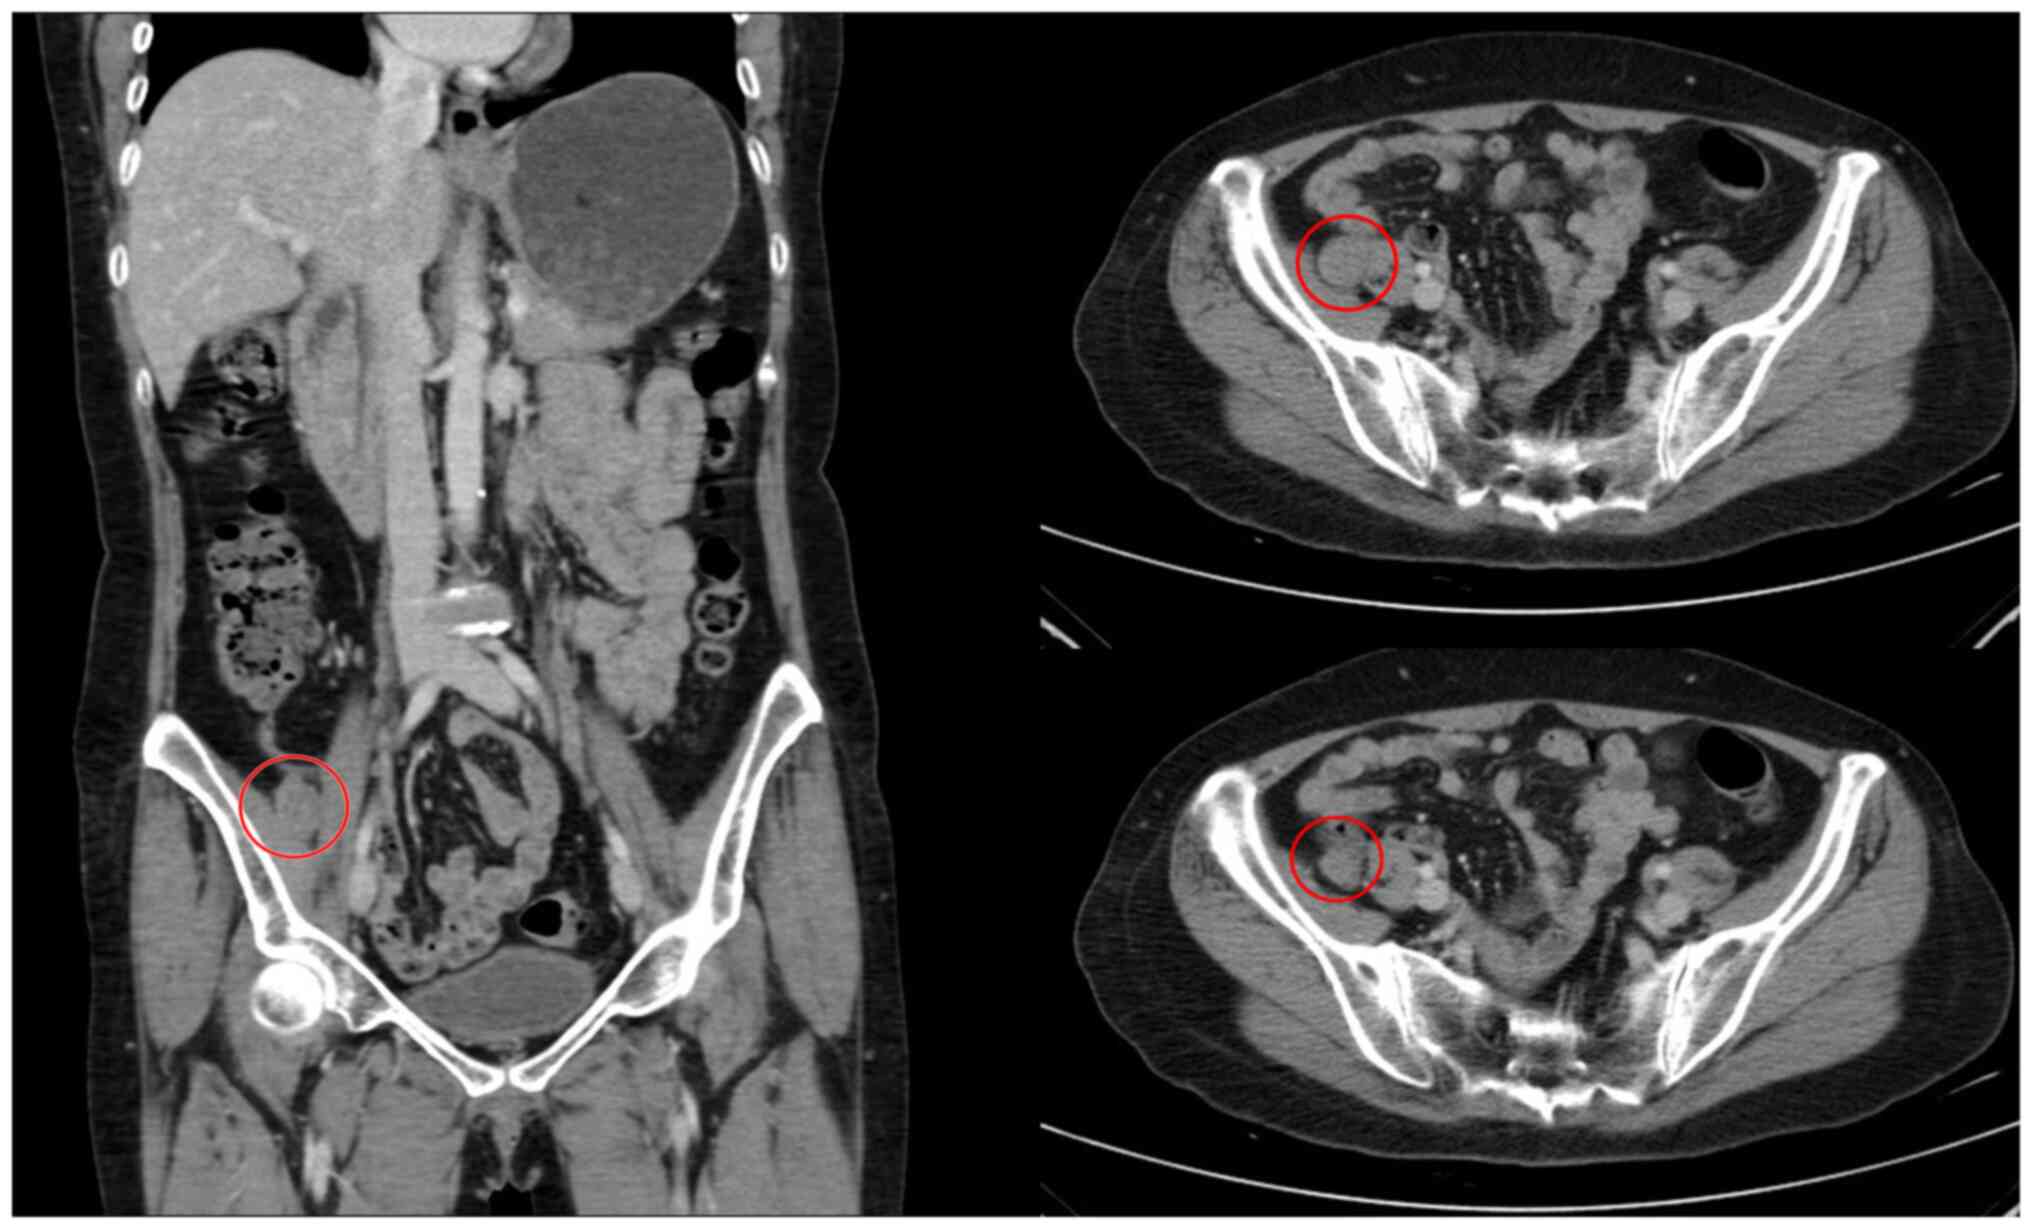

Subsequently, tissue specimens were fixed in 10% neutral buffered formalin for 24 h, dehydrated in a conventional series of gradient alcohols, made transparent with xylene, dipped in wax, paraffin embedded into paraffin tissue blocks and sectioned to 3 µm. Immunohistochemical detection was performed using an EnVision technology system (Agilent Technologies, Inc.), using a Leica Bond Max fully automatic immunohistochemistry instrument (Leica Microsystems, Inc.). The sections were examined microscopically using an Olympus light microscope (Olympus Corporation). Immunohistochemical analysis was negative for SSTR2 (clone EP149; cat. no. ZA-0587; ZSGB-BIO), E-Cad (clone MX020; cat. no. MAB-0738; Fuzhou Maixin Biotech. Co., Ltd.), EMA (clone GP1.4; cat. no. ZM-0095; ZSGB-BIO), STAT6 (clone EP325; cat. no. ZA-0647; ZSGB-BIO), CK-P (clone AE1/AE3; cat. no. Kit-009; Fuzhou Maixin Biotech, Co., Ltd.), HMB45 (cat. no. ZM-0187; ZSGB-BIO) and S100 (clone 5E2E2+4C4.9; cat. no. ZM-0224; ZSGB-BIO) (Fig. 3). The pathological diagnosis was of an intracranial myelolipoma. Postoperative renal B-ultrasonography showed no significant infiltration of both adrenal areas. Whole-abdominal enhanced CT revealed a low-density shadow in the right presacral area, which was 2.0 cm in diameter with a clear margin, and mild to moderate progressive enhancement (Fig. 4). The patient recovered well after the surgery without adjuvant therapy. The multiplicity of myelolipoma was also considered during the 3-month postoperative follow-up period. Therefore, the patient underwent a CT of the chest, an enhanced CT of the whole abdomen and an MRI of the whole spinal cord. Except for the presacral mass, the other tumors were not found on examination. To date, no tumor recurrence or metastasis has been observed.

Figure 4

Enhanced abdominal CT showing a circular mass with a slightly low-density shadow in the right presacral area, 2.0 cm in diameter, with a clear margin and mild to moderate progressive enhancement. CT, computed tomography.